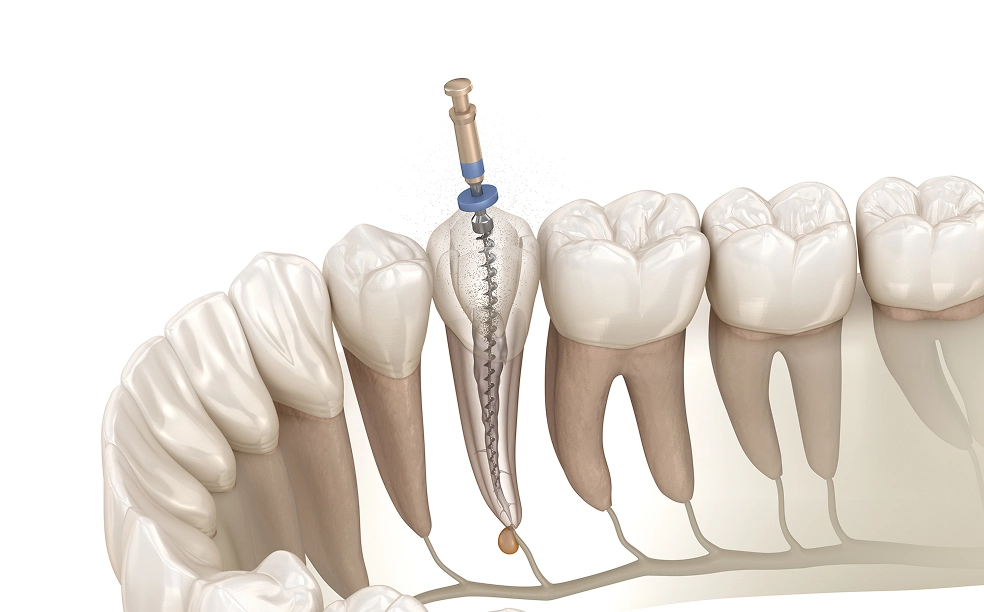

虫歯が深く進行し、歯髄に細菌が及んでいる場合、まず感染した神経や血管を取り除きます。これにより痛みや炎症を取り除き、治癒の土台を整えます。

除去後は、根管内部を専用の細い器具で丁寧に清掃し、細菌や汚れを取り除きます。その後、次亜塩素酸やEDTAなどの薬剤でしっかり洗浄・消毒し、再感染のリスクを最小限にします。